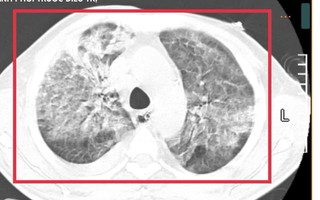

Người phụ nữ ở TP HCM bị "chết đuối trên cạn" được hàng xóm đưa đi cấp cứu kịp thời

(NLĐO) - Người bệnh sống một mình tại phòng trọ, đột nhiên đau ngực, khó thở, ngất xỉu, may mắn được hàng xóm đưa đi cấp cứu qua nguy kịch.